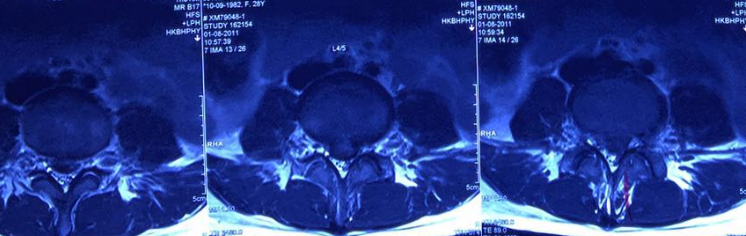

Illustrated MR 1, MR2

Severe lumbar disc herniation in the fourth and fifth segments in August 2011.